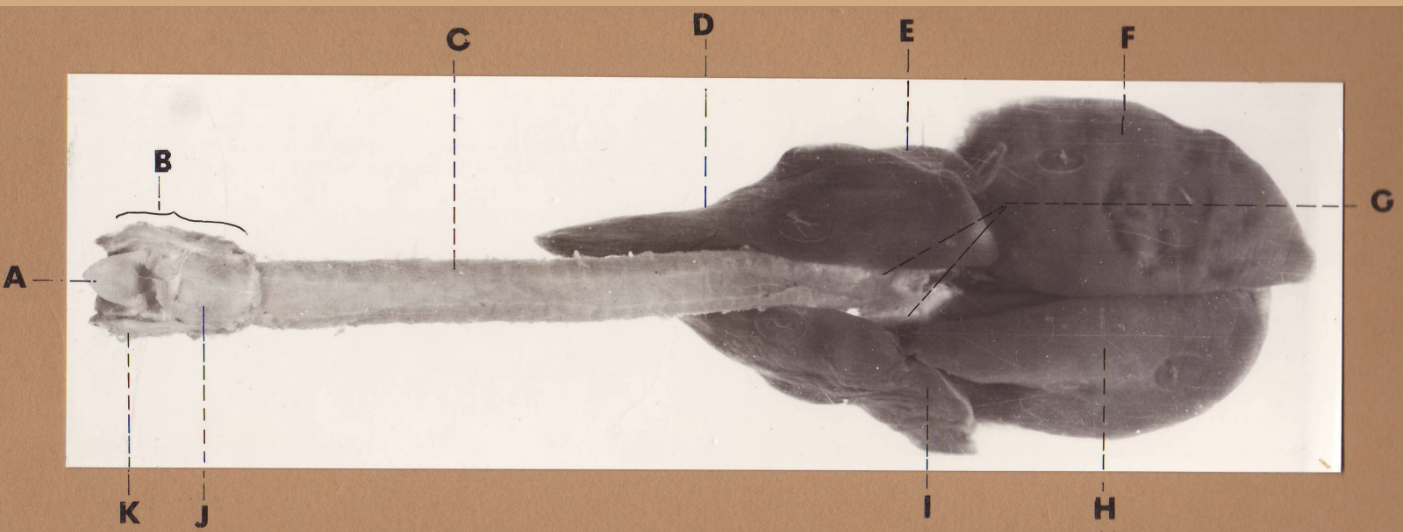

A

(cat larynx/trachea/lungs, dorsal)

epiglottis

B

(cat larynx/trachea/lungs, dorsal)

larynx

C

(cat larynx/trachea/lungs, dorsal)

trachea

D

(cat larynx/trachea/lungs, dorsal)

R cranial lobe

E

(cat larynx/trachea/lungs, dorsal)

middle lobe

F

(cat larynx/trachea/lungs, dorsal)

R caudal lobe

G

(cat larynx/trachea/lungs, dorsal)

primary bronchi

H

(cat larynx/trachea/lungs, dorsal)

L caudal lobe

I

(cat larynx/trachea/lungs, dorsal)

L cranial lobe

J

(cat larynx/trachea/lungs, dorsal)

cricoarytenoideus dorsalis m

K

(cat larynx/trachea/lungs, dorsal)

thyroid

A

(cat larynx/trachea/lungs, dorsal)

epiglottis

B

(cat larynx/trachea/lungs, dorsal)

larynx

C

(cat larynx/trachea/lungs, dorsal)

trachea

D

(cat larynx/trachea/lungs, dorsal)

R cranial lobe

E

(cat larynx/trachea/lungs, dorsal)

middle lobe

F

(cat larynx/trachea/lungs, dorsal)

R caudal lobe

G

(cat larynx/trachea/lungs, dorsal)

primary bronchi

H

(cat larynx/trachea/lungs, dorsal)

L caudal lobe

I

(cat larynx/trachea/lungs, dorsal)

L cranial lobe

J

(cat larynx/trachea/lungs, dorsal)

cricoarytenoideus dorsalis m

K

(cat larynx/trachea/lungs, dorsal)

thyroid